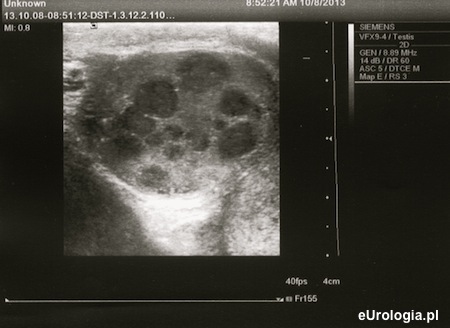

Fot. Rak jądra - liczne ogniska guza w USG moszny